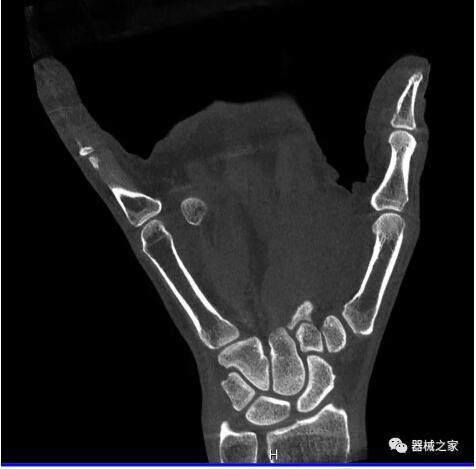

以下是這些“特立獨(dú)行”的CT所拍出來(lái)的圖像: